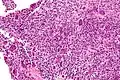

High magnification micrograph of an aneurysmal bone cyst Intermediate magnification micrograph of an aneurysmal bone cyst

Intermediate magnification micrograph of an aneurysmal bone cyst